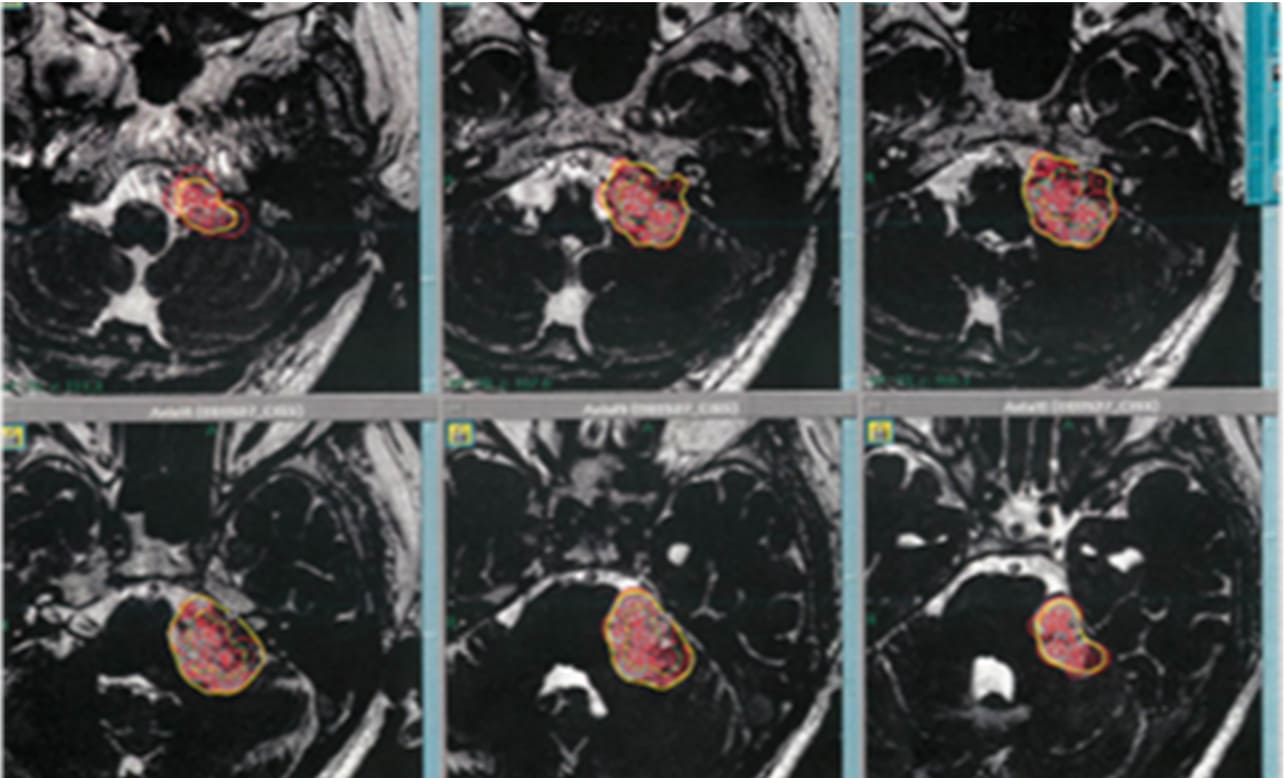

巨大のう胞性聴神経腫瘍症例に対する治療計画

聴神経腫瘍1400症例中、外科手術を要したのは実に6名のみ(いまのところ術中に強い癒着を呈していたという報告はありません)。一方で、大方の患者さんは6か月後に一過性膨大を伴います。これは高線量一括照射に伴う腫瘍内部の栄養血管が強い炎症反応(血管炎)を呈することが主因であり、腫瘍が成長し続ける腫瘍増大とは異なります。腫瘍中心に造影欠失像(Loss of central enhancement/LCE)として描出されることが特徴となっています。

他の神経鞘腫には同様に認められますが、髄膜腫など他の脳腫瘍にはまず認められない特徴的な所見となっています。その際に、初動時のふらつきを訴える患者さんもおりますが、難聴や顔面麻痺などは通常起こりません。この炎症反応はさらに6か月後には収まり、治療時とほぼ同サイズへと戻ります。その後1-2年して、全体の75%ほどが縮小傾向に入り、10年経てもさらに縮小し続けるのが特徴となっています。